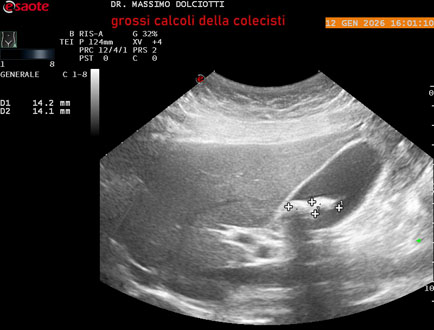

Data inserimento: 14/01/2026

Ecografia del: 12/01/2025

Strumento: Esaote MyLab Eight

Sonda: Convex Multifrequenza 1-8 MHz

Età Paziente: F 45 anni

Motivazione dell'esame: nicturia 1-2 volte.

Commento all'esame: le immagini ed il video documentano nel lume della colecisti, due immagini iperecogene, con cono d'ombra posteriore, delle dimensioni di 20,9 mm e 15,7 mm, da ricondurre a litiasi multipla.

Conclusioni: grossi calcoli della colecisti (large gallstones).

In collaborazione: Dr.ssa Marica Manfredi - Ancona, Dr. Ilir Qose - Ancona

Presentazione: Dr. Massimo Dolciotti - Ancona

Elaborazione digitale: Andrea Dini - Ancona